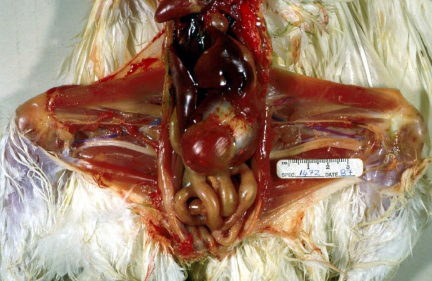

Post-mortem of heavily pregnant ewe found dead. Pregnant with 3 lambs. Diagnosis?

Ketosis/Pregnancy toxaemia/twin lamb disease. Causes hepatic lipidosis.